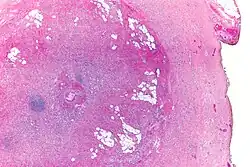

| Micrograph showing a goblet cell carcinoid. H&E stain. | |

The goblet cell carcinoid (GCC) is a rare biphasic gastrointestinal tract tumour that consists of a neuroendocrine component and a conventional carcinoma, histologically arising from Paneth cells.[1]

GCCs are diagnosed by pathology. They have a characteristic biphasic appearance which includes (1) goblet cell-like cells, and (2) neuroendocrine-type nuclear chromatin (stippled chromatin).